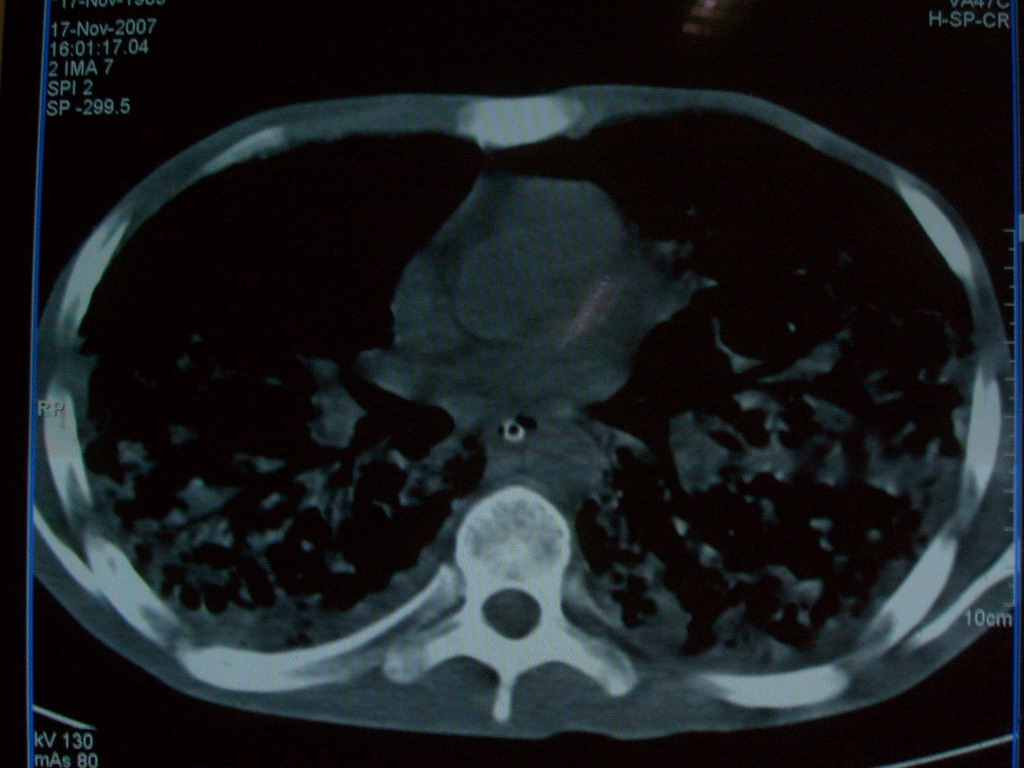

标题: CT10510:男.18岁,咳嗽咳痰两月.(有病理) [打印本页]

标题: CT10510:男.18岁,咳嗽咳痰两月.(有病理)

双肺布满大片状实变及网格状结节影,内参杂大小不等的气囊及空气支气管征,心脏增大。考虑:1 全身结缔组织疾病—系统性红斑狼仓?2 肺泡蛋白沉积症合并感染!

双肺布满大片状实变及网格状结节影,内参杂大小不等的气囊及空气支气管征,双侧胸膜腔少量积液,双下肺近膈面透亮度尚可,病人较年轻,病变较重(不知为什么上胃管?)考虑:1.胶原病肺部改变,2.组织细胞病x。结合实验室检查。

首先考虑组织细胞x病。两肺中上肺野多发囊腔,中下肺野内见多发小结节,并可见肺间质增厚。患者是男性,年龄较小。胶原性病变比较多见的类风湿、系统性红斑狼疮和硬皮病临床和影像均不是很支持,类风湿和系统性红斑狼疮的肺部表现最常见的是胸腔积液,硬皮病可见食管的扩张。

肺内多发斑片状、结节状、融合大片状及网格状影,多发薄壁空腔影,胸膜肥厚,纵隔、气管右移,考虑ⅲ型肺结核,多发空洞,继发肺间质纤维化。

双肺结核并播散.患者以肠梗阻入院,手术为肠结核.术后咳嗽做ct检查.